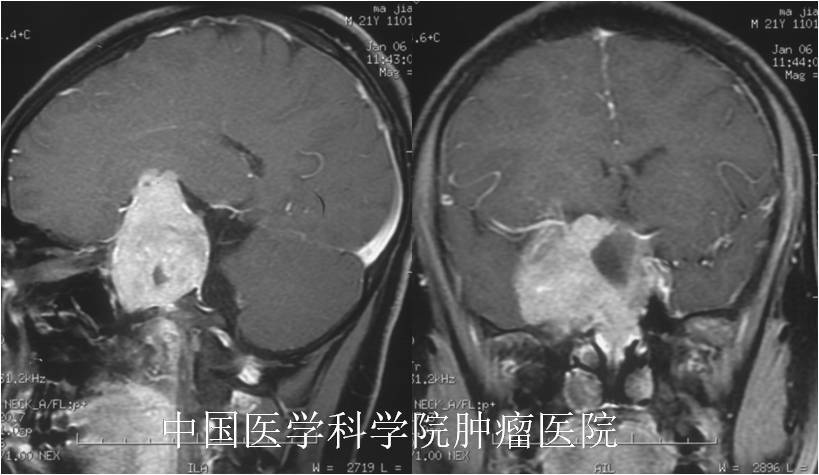

摘要:因“雙眼視力下降半年、頭痛嘔吐1周”就醫(yī)的年輕男性,檢查后發(fā)現(xiàn)是顱內(nèi)外溝通的巨大垂體泌乳素腺瘤,門診建議患者口服溴隱亭治療;患者和家屬很想手術(shù)切除,但經(jīng)過我的耐心解釋,患者和家屬還是欣然同意首先藥物治療?;颊吆苄疫\,口服溴隱亭后腫瘤基本消失、垂體激素也基本正常。藥物治療是垂體泌乳素腺瘤的首選治療方案,但對于部分藥物耐受困難、治療效果不佳或治療期間出現(xiàn)卒中出血的患者,也應該考慮積極手術(shù),保護患者功能?!净拘畔ⅰ磕?,23歲【疾病類型】垂體瘤-藥物治療【就診醫(yī)院】中國醫(yī)學科學院腫瘤醫(yī)院【就診時間】2015-1【治療方案】口服藥物溴隱亭2-8片/天保守治療,根據(jù)激素水平和復查結(jié)果調(diào)整劑量?!局委熤芷凇块L期口服藥物,每半年門診隨訪。【治療效果】藥物治療后腫瘤基本消失、垂體激素也基本正常,視力明顯改善。一、初次面診患者是個年輕男性,初次門診就診時有明顯的焦慮和痛苦表情?;颊甙肽昵俺霈F(xiàn)雙眼視力進行性下降,因為經(jīng)常用電腦工作、本身又近視,因此沒有重視;這期間患者老是覺得渾身乏力,飲食也不好。1周前患者突然頭痛、伴惡心嘔吐,當外院急診就診,行頭顱CT:提示顱底巨大腫瘤?;颊邇?nèi)心非常焦慮、害怕,于是來到我院就診,尋求進一步治療。我對患者適當安慰,告訴他大概率是個良性腫瘤,患者才稍微輕松點。二、治療經(jīng)過??患者來院時一般情況尚可,入院查體:神志清楚,精神好,應答切題,遵囑活動,定向準確。粗測雙眼視力明顯下降,粗測雙側(cè)顳側(cè)視野明顯缺損。雙瞳孔等大等圓直徑3mm,對光反射靈敏。右側(cè)眼球外展受限,自訴有復視。雙側(cè)額紋鼻唇溝對稱,口角無歪斜,伸舌居中。頸軟,腦膜刺激征(-)。四肢肌力肌張力正常,雙側(cè)巴氏征(-)。??為了進一步明確病變部位和性質(zhì),進行頭顱MRI檢查,結(jié)果提示:蝶竇-斜坡-鞍區(qū)-鞍上-右側(cè)海綿竇巨大腫瘤,形態(tài)欠規(guī)則、邊界尚清,呈等長T1、等長T2信號,增強后明顯均勻強化;瘤內(nèi)可見囊變壞死。完善了垂體激素、皮質(zhì)醇等化驗:提示泌乳素PRL>10000uIU/ml,皮質(zhì)醇偏低。根據(jù)病史和臨床癥狀,并結(jié)合頭顱MRI的結(jié)果,初步診斷為巨大垂體泌乳素腺瘤。建議患者口服溴隱亭藥物治療,同時充分向患者和家屬交代了藥物治療可能的并發(fā)癥和治療風險,告知其如藥物治療效果不佳要積極考慮手術(shù)。患者從2015-8開始口服溴隱亭治療,初始劑量1片/次、2次/天;后期根據(jù)復查的垂體激素結(jié)果逐漸增量至4片/次,2次/天;后來又逐漸減量,現(xiàn)在口服藥物半片/次、2次/天小劑量維持。三、治療效果??患者治療效果非常滿意,藥物反應和藥物耐受性都很好。開始口服藥物后泌乳素下降很快,腫瘤也明顯縮小,患者的視力視野明顯改善、體力和飲食也基本正常。1年前復查時,復查頭顱MRI:腫瘤已經(jīng)基本消失;患者雙眼視力視野基本正常,生活工作也早已恢復正常。四、注意事項1、治療期間要積極配合醫(yī)生調(diào)整身體狀況,保證充足的睡眠。2、治療期間要配合醫(yī)生完善頭顱CT、MRI等輔助檢查,以明確腫瘤變化,制定合理的治療方案。3、腫瘤皺縮后可能引起自發(fā)性腦脊液鼻漏,保持大便通暢、避免咳嗽打噴嚏,防止腦脊液漏。4、嚴格根據(jù)醫(yī)囑用藥,保證治療效果。5、如有發(fā)熱、頭痛、惡心、嘔吐等不適癥狀,及時就近就診。6、定期門診復查頭顱MRI、垂體激素和皮質(zhì)醇等。?五、個人感悟垂體瘤是最為常見的鞍區(qū)腫瘤。由于腫瘤會壓迫視神經(jīng)、視交叉、垂體和垂體柄,多有視力減退、視野缺損、內(nèi)分泌異常等臨床癥狀。多數(shù)垂體瘤應考慮手術(shù)切除。但是,泌乳素腺瘤是一類比較特殊的功能性腺瘤,口服溴隱亭藥物治療是泌乳素腺瘤的首選治療方案。部分巨大的泌乳素腺瘤手術(shù)風險很高,但是藥物治療相對安全、甚至能取得非常滿意的治療效果。本例患者就是一個典型藥物治療成功的病例。患者腫瘤非常大、廣泛侵犯顱內(nèi)和顱底,直接手術(shù)風險很高;幸而患者是泌乳素腺瘤,口服溴隱亭后治療效果非常滿意,腫瘤基本消失,患者的神經(jīng)功能也得到了很好的保護。但溴隱亭可能有一系列的副作用:1.許多患者服藥后可能會發(fā)生惡心、嘔吐、頭痛、眩暈或疲勞;2.極少數(shù)病例中服用本品后發(fā)生體位性低血壓;3.在大劑量治療時,可能會發(fā)生幻覺、意識精神錯亂、視覺障礙、運動障礙、口干、便秘、腿痙攣等,這些副作用約為劑量依賴性,減量就能夠使癥狀得到控制;4.在長期治療中,特別對于有雷諾氏現(xiàn)象病史者,可能偶發(fā)可逆性低溫誘發(fā)指趾蒼白;5.部分患者比較大劑量服用常出現(xiàn)頭暈、頭痛、惡心嘔吐等癥狀,難以耐受,導致藥物治療難以達到治療劑量或持續(xù)。但對于部分藥物耐受困難、治療效果不佳、或有卒中出血導致急性視力損傷的患者,要積極考慮手術(shù)切除。